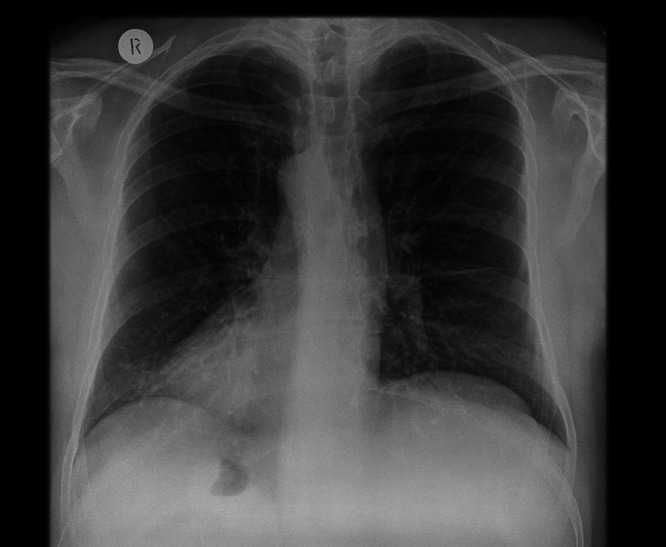

Abstract Image